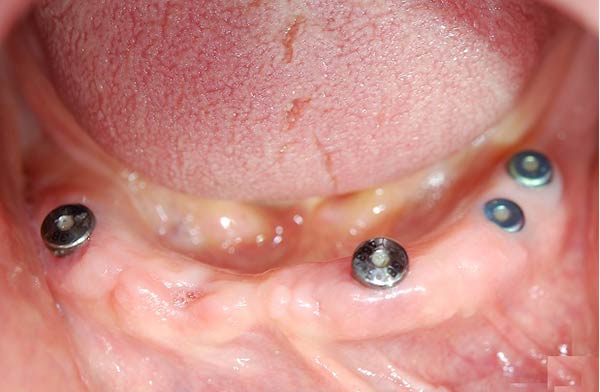

I denti irrecuperabili dell'arcata superiore ed inferiore del paziente di anni 65

sono stati sostituiti da 10 impianti, cioè protesi radicolari endo-ossee che sostengono le protesi fisse superiore ed inferiore.